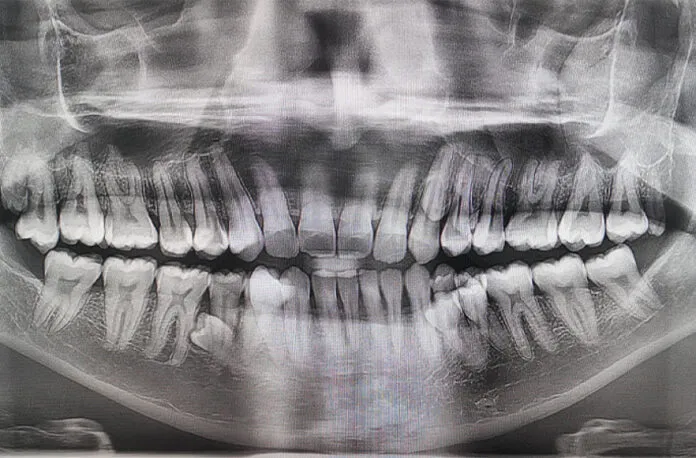

Muniandiniň sözlerine görä, ol bu aýratynlygy ilkinji gezek 2021-nji ýylda çaý başynda bilipdir, ol dogan-garyndaşlaryna özünde artykmaç dişleriň bardygyny aýdypdyr. Olar dişleri sananlarynda, 38 ekeni. Soňra rentgen barlagynda erkek kişiniň ýene dört dişiniň ösüp gelýändigi belli bolupdyr. 2023-nji ýylda bolsa olaryň sany 42-ä ýetipdir. Prathab dişleriniň deň ösýändigini we hiç hili biynjalyk etmeýändigini gürrüň berýär.

Ginnesiň kitabyna resmi hasaba almak üçin barlag wagtynda stamotologlar garaşylmadyk ýagdaýy – malaýziýalynyň heniz et ýarmadyk ýene iki dişiniň bardygyny anyklapdyrlar.